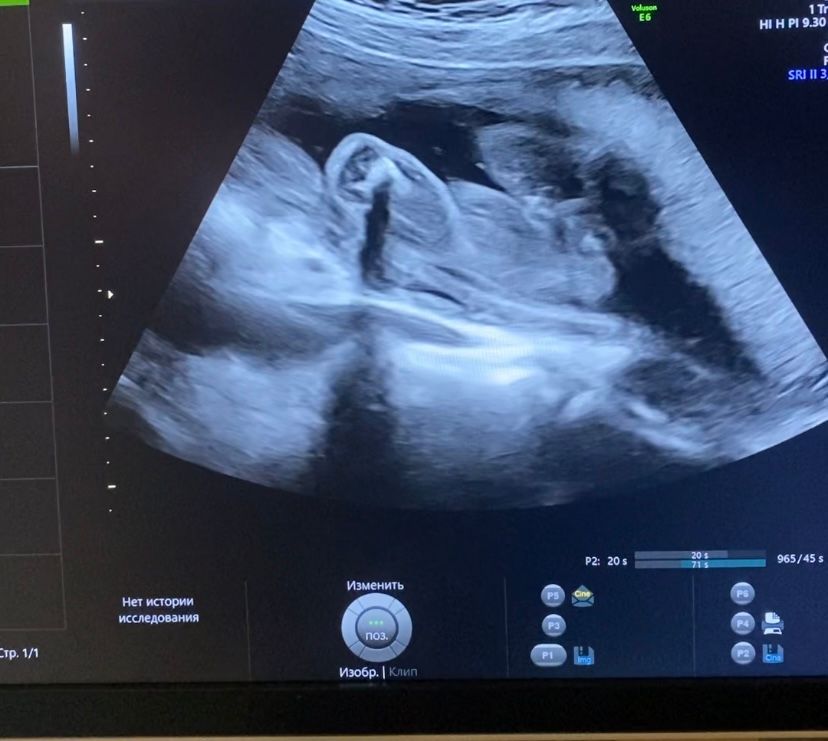

Мальчик или девочка????

Вчера был второй скрининг. И вот я попросила пол на бумажке написать.

Изображение